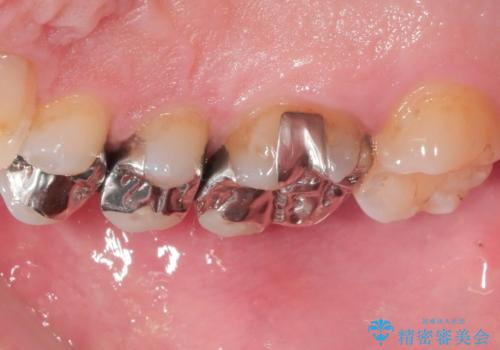

- 銀歯のセラミックへのやり替えをご希望で来院されました。

銀歯が入ってる歯は複数箇所ありましたが、咬合力がより強く破折リスクが高い奥歯から治療を開始してます。

奥歯の噛み合わせが強く、治療後にセラミックが割れるリスクがあった為マウスピースの装着をして頂いてます。